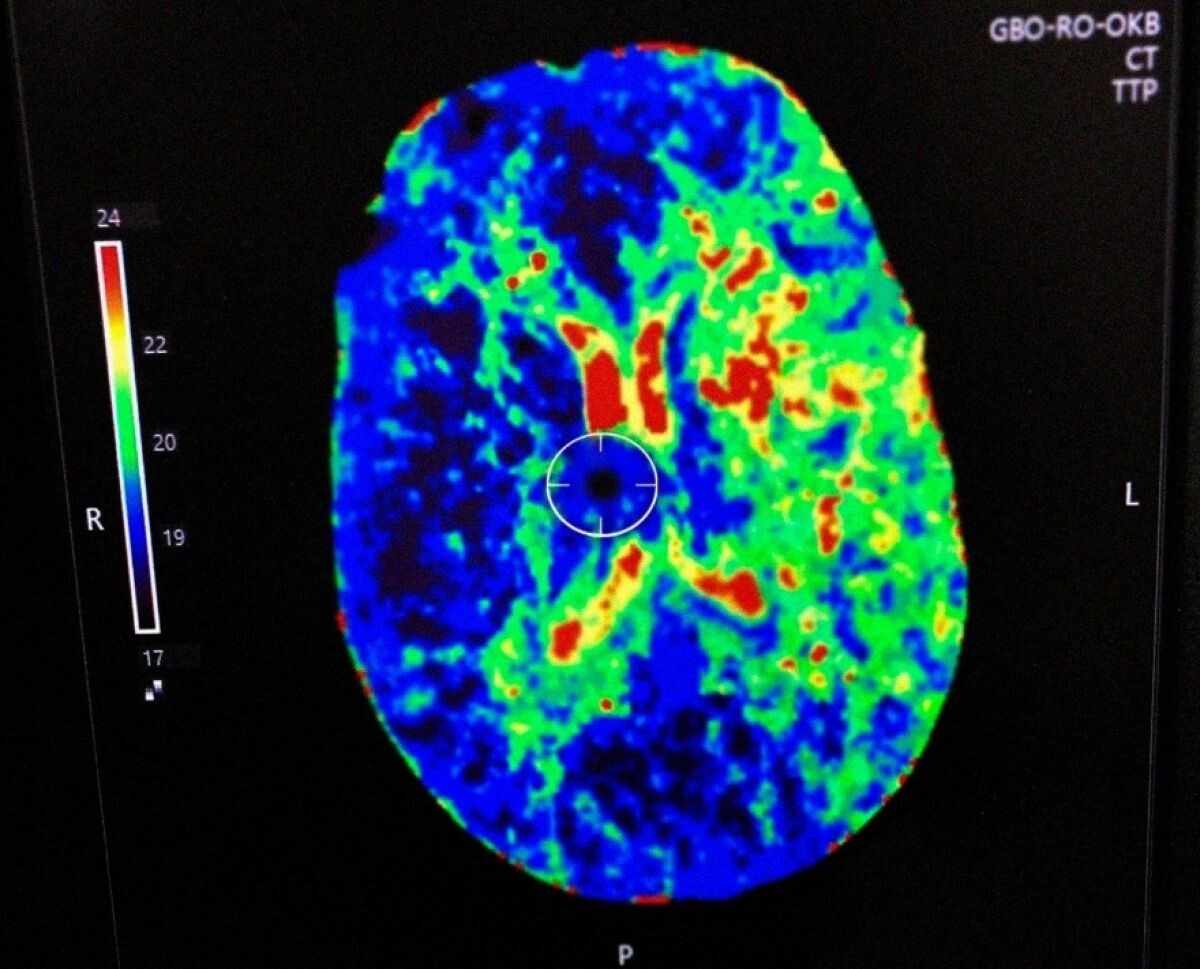

Прибывшая бригада медиков заподозрила инсульт и экстренно доставила пациента в областную клиническую больницу. Диагноз подтвердился, после чего мужчину начали готовить к проведению тромболитической терапии. В ходе сбора анамнеза выяснилось, что пациент периодически курил — бросал вредную привычку, но затем возвращался к ней снова.